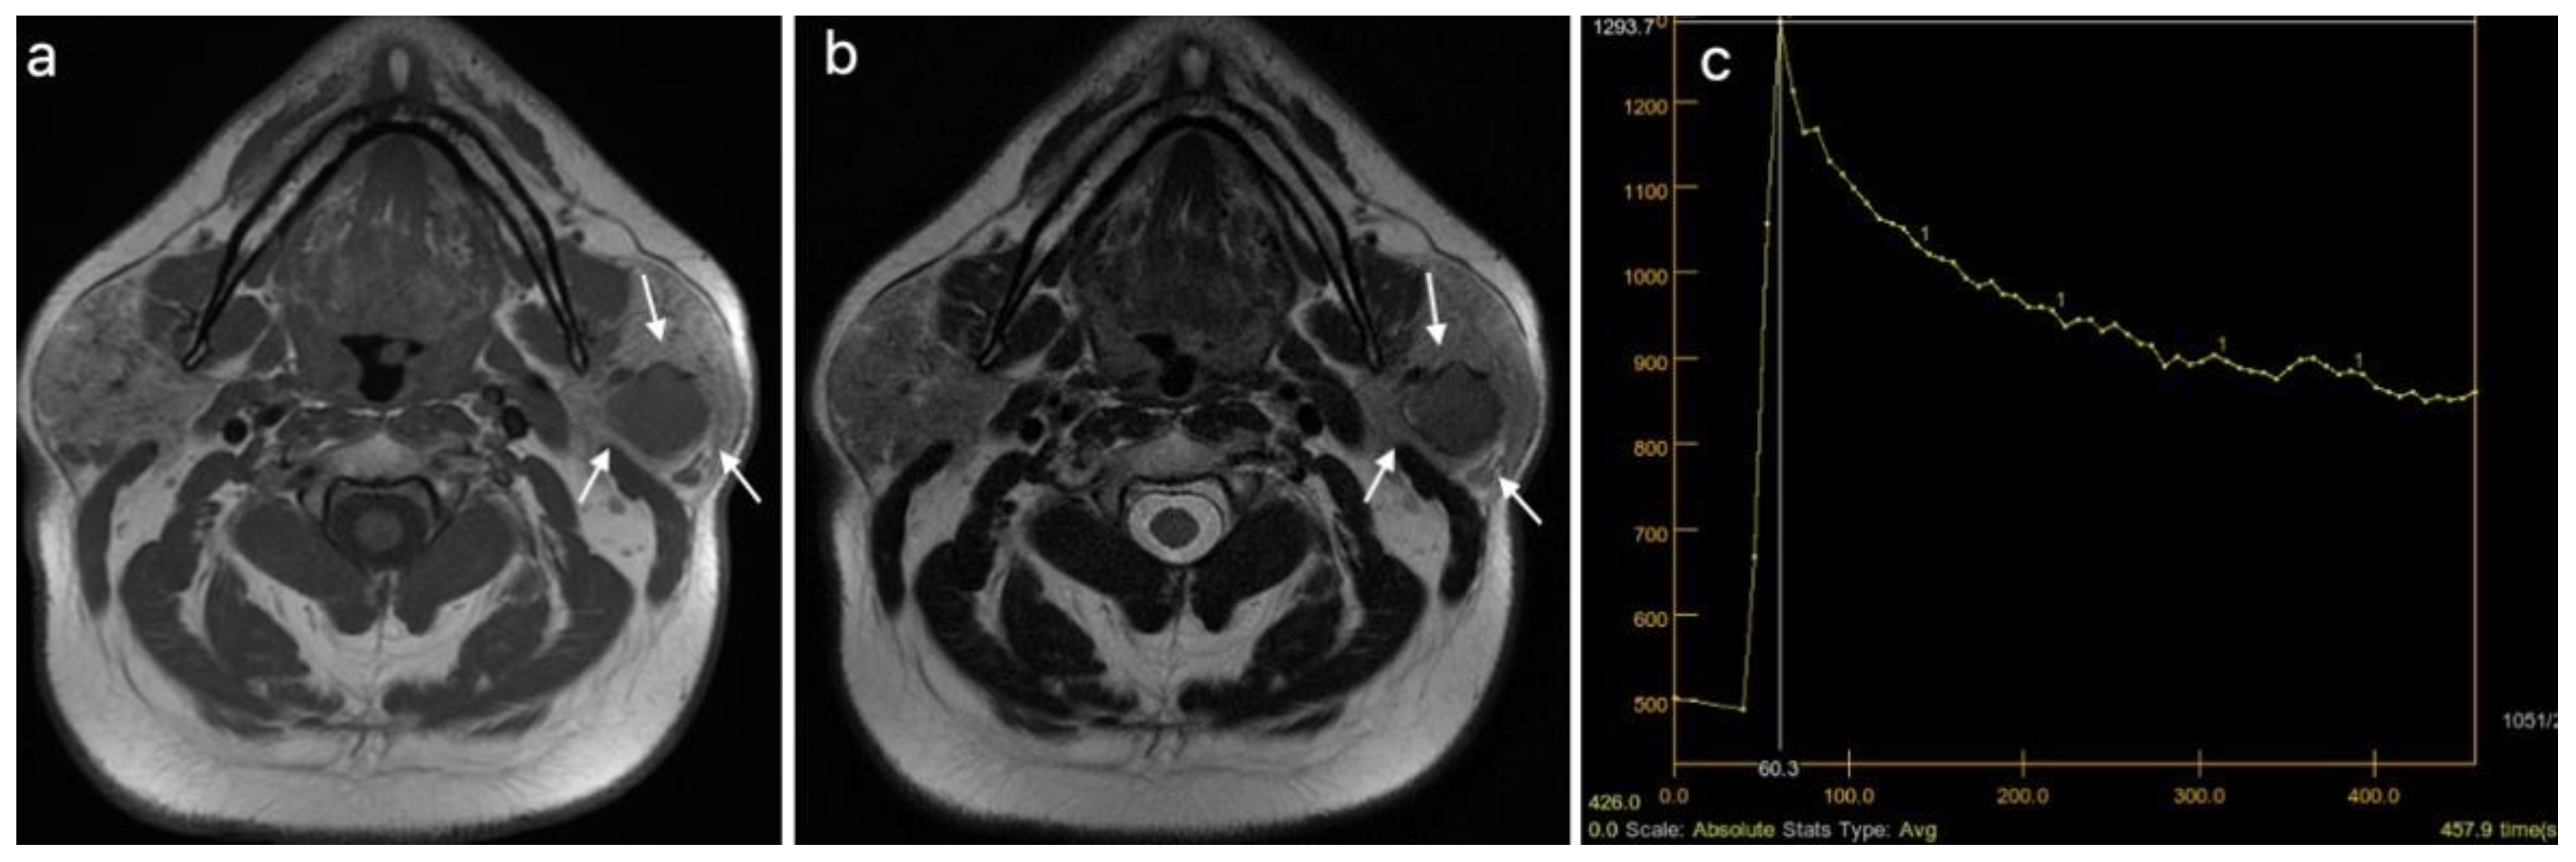

| DCE MRI*–TIC curve+, n (%) | 0.382 | ||

| Type A | 16 (29.63) | 1 (9.09) | |

| Type B | 18 (33.33) | 5 (45.45) | |

| Type C | 20 (37.04) | 5 (45.45) | |

| DCE MRI, TIC curve grouped (A, B vs. C), n (%) | 34 (62.96) | 6 (54.5S5) | 0.737 |

| DCE MRI, TIC curve, n (%) | <0.001 | ||

| Type A | 14 (73.68) | 0 (0) | |

| Type B | 3 (15.79) | 11 (37.93) | |

| Type C | 1 (5.26) | 18 (62.07) | |

| DCE MRI, TTP (ms), median (IQR) | 210 (166.15–228.9) | 88.5 (82–101.9) | <0.001 |